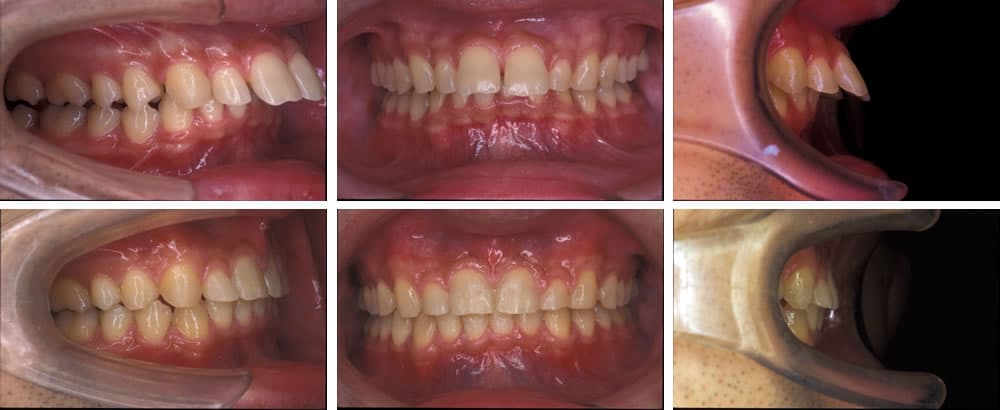

開咬(オープンバイト)

開咬は上下の歯を咬み合わせた際、前歯が咬み合わずに隙間ができてしまう歯並びです。正しい咀嚼ができないため、胃腸などの消化器官に負担がかかります。また、口腔内が乾燥しやすく、唾液の殺菌作用が低下するため、虫歯・歯周病リスクが高くなります。